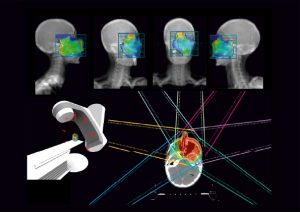

Plan Review | Doz Planınız Her Yönden İncelenebilir

MIM Maestro ile tüm tedavi planlarınızı tek bir yerde inceleyebilirsiniz.

İncelenebilen bileşenler:

- Konturlar

- İzodoz grafikleri

- DVH (Doz Hacim Histogramları)

- Işın açıları

- Işın gözünden görüntü

- Oda gözünden görüntü

- DRR (Dijital Rekonstrüksiyon Radyografi) görüntüleri

MIM, marka ayrımı yapmadığı için tedavi planlarınızı herhangi bir TPS’den (Tedavi Planlama Sistemi) aktarabilirsiniz.

MIM Maestro Plan Review özelliği, bir tıklama ile plan hazırlama olanağı sunmaktadır.

Planları ofisinizde, cep telefonunuzda veya tabletinizde inceleyebilirsiniz.